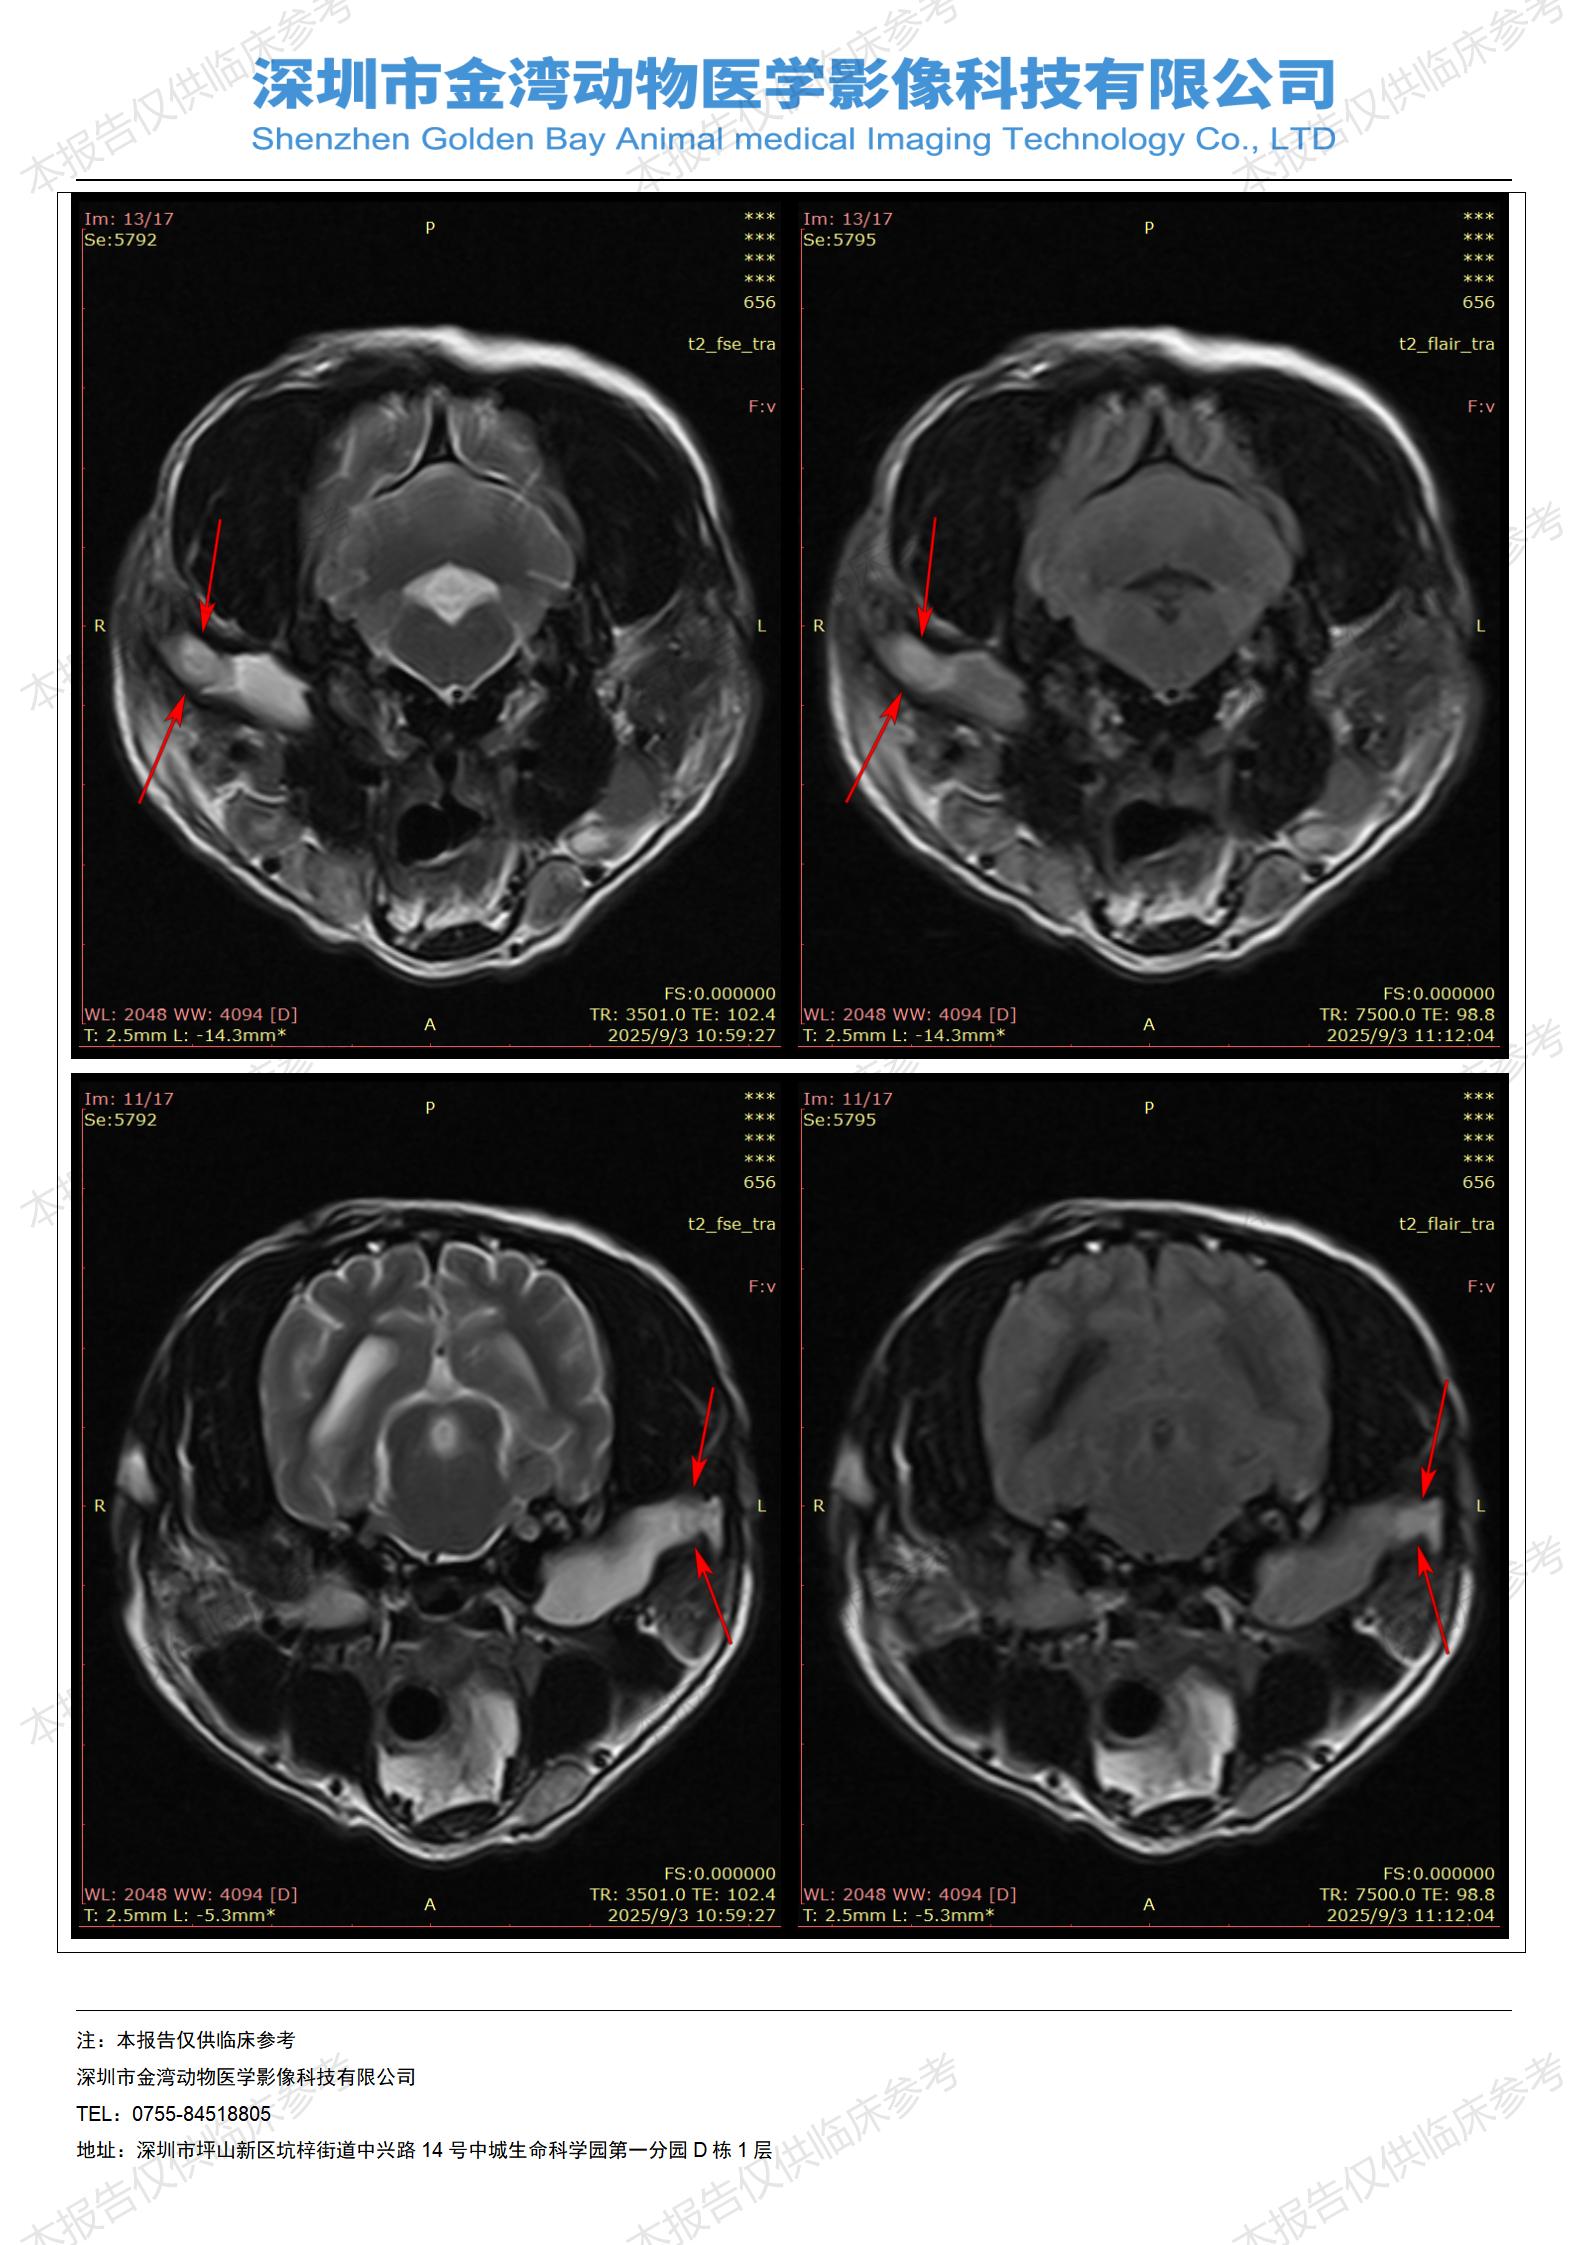

金石医疗MRI影像诊断案例:一例狗双耳流脓的诊断报告